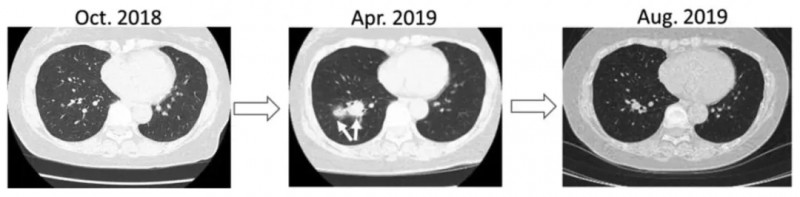

病例6(74岁男性肾癌肺转移患者)

该患者于2018年7月术后2个月出现多发肺转移,因肺静脉血栓无法使用靶向药,2019年1月起接受新抗原肽脉冲DC疫苗治疗。

结果显示:接种3剂后获得部分缓解(PR)。接种完六剂疫苗后,几乎获得完全缓解(CR),肿瘤完全消失。2020年8月复查CT,证实该患者获得了持久完全缓解(CR)(详见下图)。

▲图源“Anticancer research”,版权归原作者所有,如无意中侵犯了知识产权,请联系我们删除